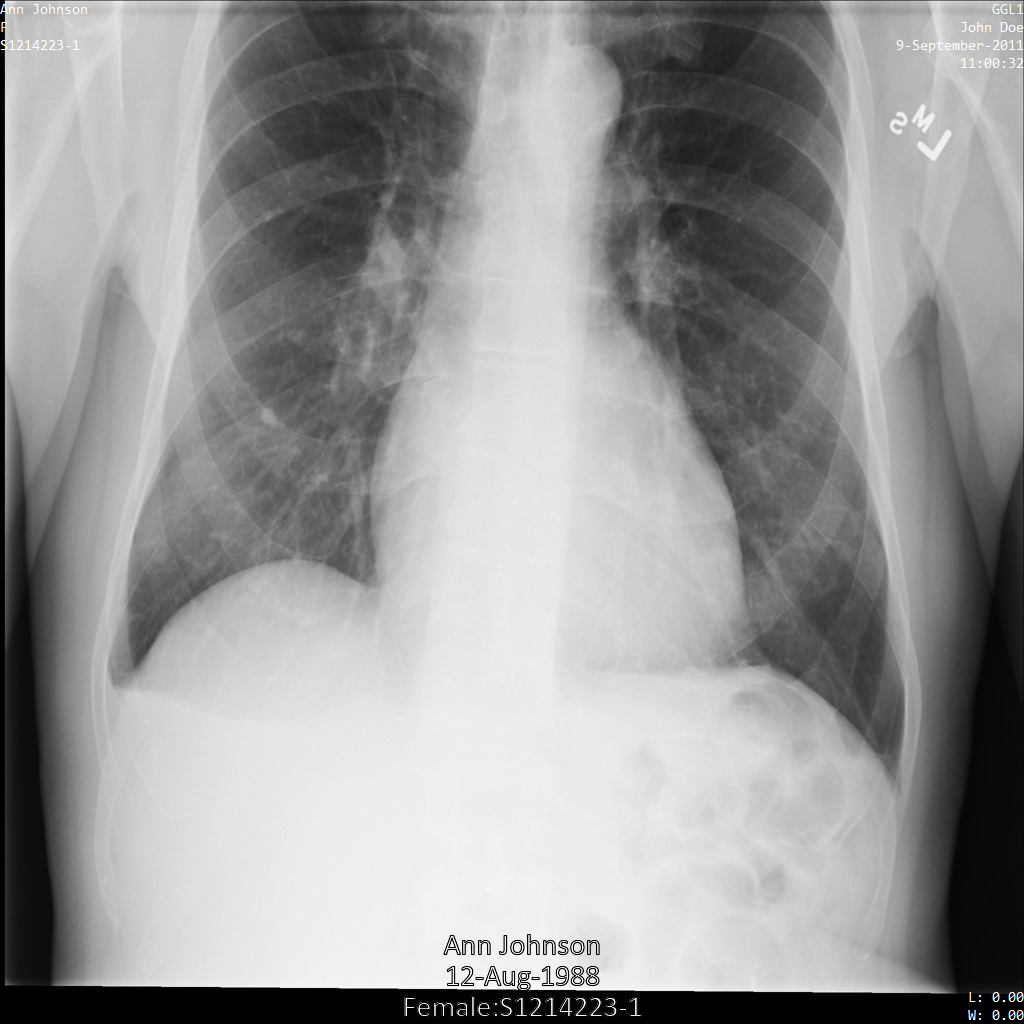

Une fois l'image envoyée à l'API Cloud Healthcare, elle apparaît comme suit. À l'exception des balises fournies dans la liste de suppression, seul PatientBirthDate est supprimé dans l'image, car il s'agit de la seule balise de la liste de suppressions qui correspond aux métadonnées visibles dans l'image.

Bien que le PatientBirthDate dans l'angle supérieur de l'image ait été masqué conformément à la configuration de la liste removelist, les données de santé protégées incrustées en bas de l'image sont conservées. Pour supprimer également le texte incrusté, consultez la section Masquer le texte incrusté dans les images.

dicom_removelist